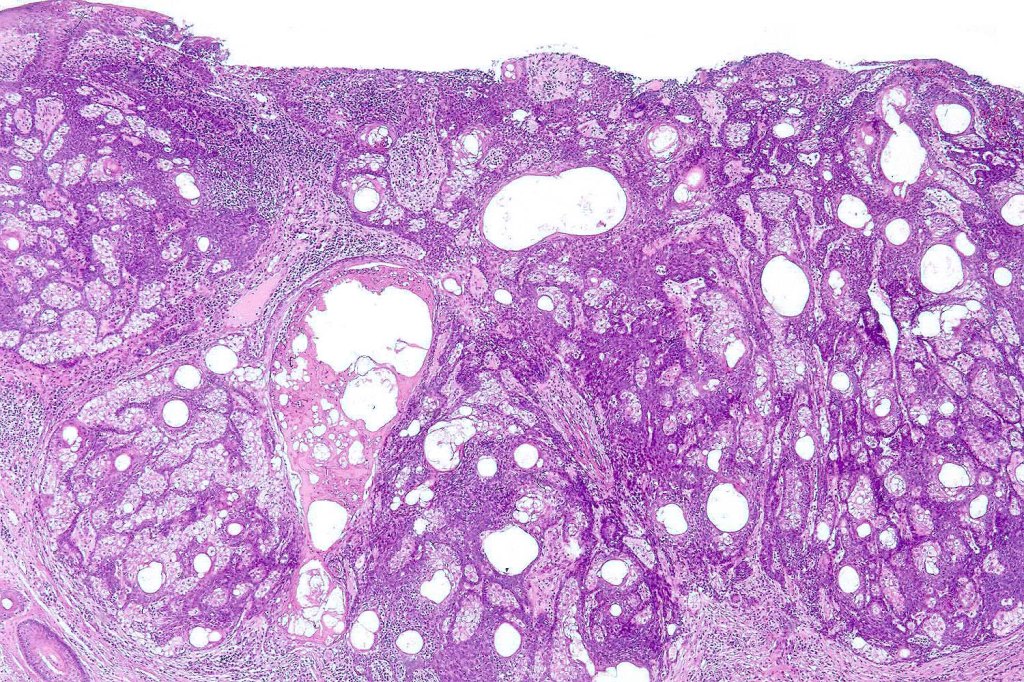

Histological features

•Variable continuity with epidermis

•Multinodular with surrounding collagenous stroma

•Random distribution of basaloid cells & sebocytes (<50% sebocytes)

•Duct formation, often with holocrine secretion generally present

•Mitoses sparse to conspicuous

•Absent peripheral palisading & retraction artifact

•Cystic variant

•Subtypes include rippled pattern, carcinoid-like & reticulated